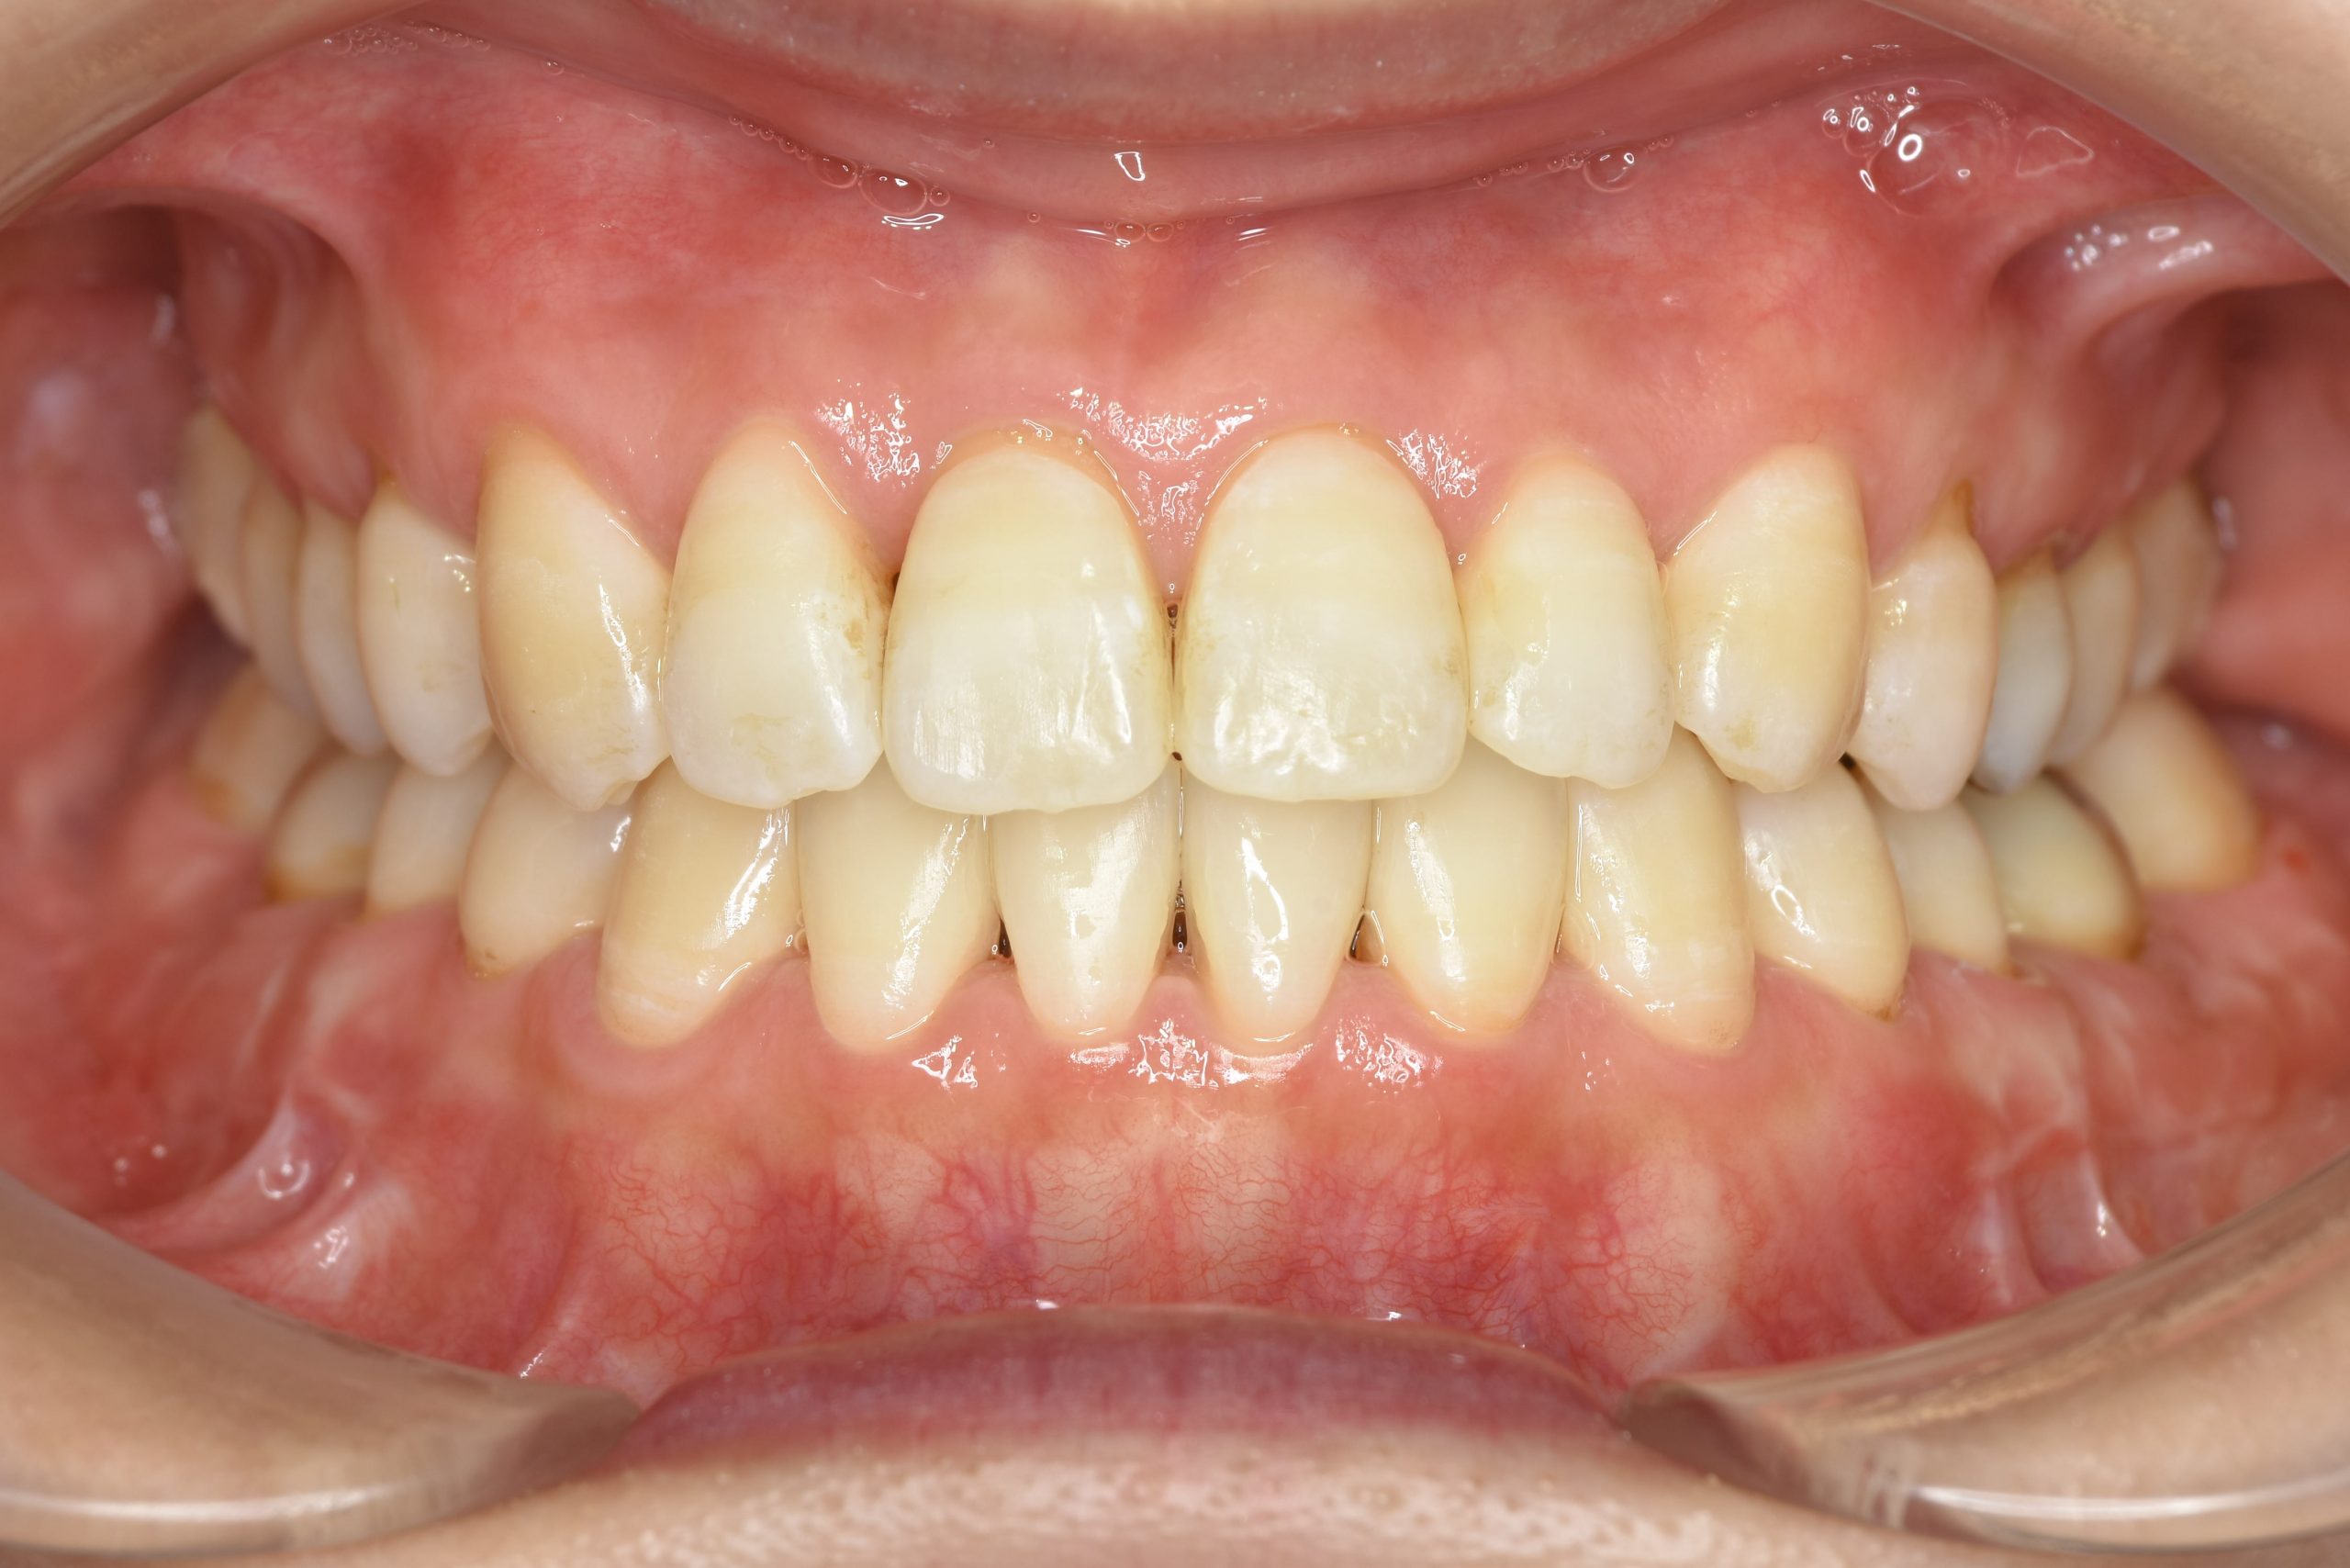

ビフォー

保険での矯正治療|症例_138

主訴 噛み合わせが悪い(反対)|歯並びが悪い|顎が出ている

施術内容 マルチブラケット装置を用いて歯牙を配列した後、

下顎骨離断術を行った。良好な咬合を獲得した。

治癒期間 3年8ヶ月間

費用 保険治療

リスク・副作用 違和感、不快感、痛み